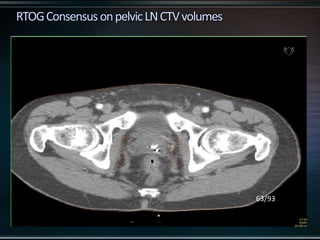

RTOG GU Consensus on pelvic LN CTV volumes:

 Commence contouring the pelvic CTV LN volumes at the L5/ S1

interspace (the level of the distal common iliac and proximal

presacral lymph nodes).

 Place a 7-mm margin around the iliac vessels connecting the

external and internal iliac contours on each slice, carving out

bowel, bladder, and bone.

 Contour presacral lymph nodes from S1 through S3, posterior

border being the anterior sacrum, and anterior border

approximately 10 mm anterior to the anterior sacral bone

carving out bowel, bladder, and bone.

 Stop external iliac CTV lymph node contours at the top of the

femoral heads (bony landmark for the inguinal ligament).

 Stop contours of the obturator CTV lymph nodes at the top of

the symphysis pubis.

RTOG GU Consensuson pelvic LN CTV volumes:  Commence contouring the pelvic CTV LN volumes at the L5/ S1 interspace (the level of the distal common iliac and proximal presacral lymph nodes).  Place a 7-mm margin around the iliac vessels connecting the external and internal iliac contours on each slice, carving out bowel, bladder, and bone.  Contour presacral lymph nodes from S1 through S3, posterior border being the anterior sacrum, and anterior border approximately 10 mm anterior to the anterior sacral bone carving out bowel, bladder, and bone.  Stop external iliac CTV lymph node contours at the top of the femoral heads (bony landmark for the inguinal ligament).  Stop contours of the obturator CTV lymph nodes at the top of the symphysis pubis.